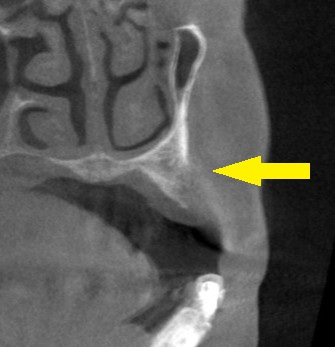

抜歯後3か月でCTを撮ってみたのですが、骨の幅も、高さも足りません(下の写真2段目)。

上方へ少し骨を持ち上げる方法と、頬側には人工骨を補填する方法を併せて行い、インプラント埋入を行なうこととしました。